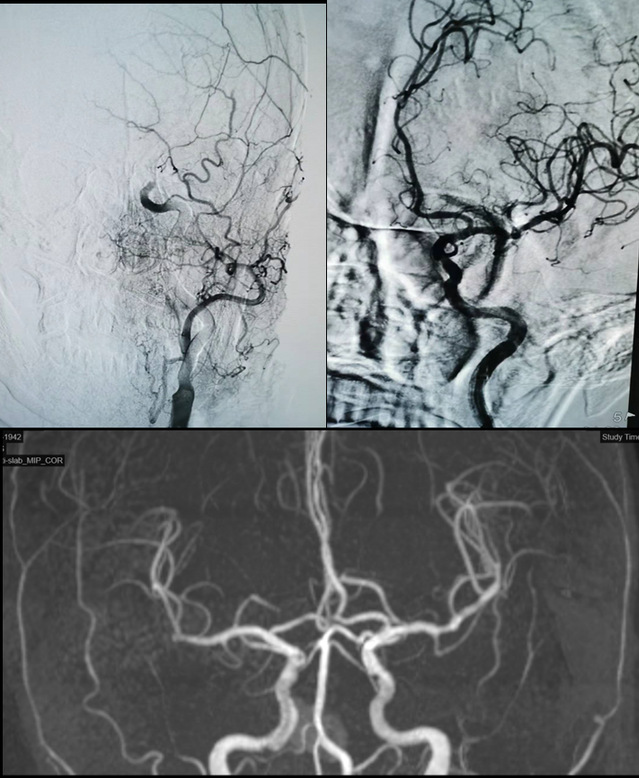

抵达医院后,医院开启卒中绿色通道,并完善急诊头颅CT等检查,最终被诊断为“急性脑栓塞”。最后,在卒中团队的统筹安排下,病人被迅速送至手术室,进行了脑动脉取栓手术。术中造影发现患者一侧大脑中动脉闭塞,手术团队运用支架联合抽吸导管技术,成功取出血栓,术后沈大爷的肢体偏瘫情况好转。